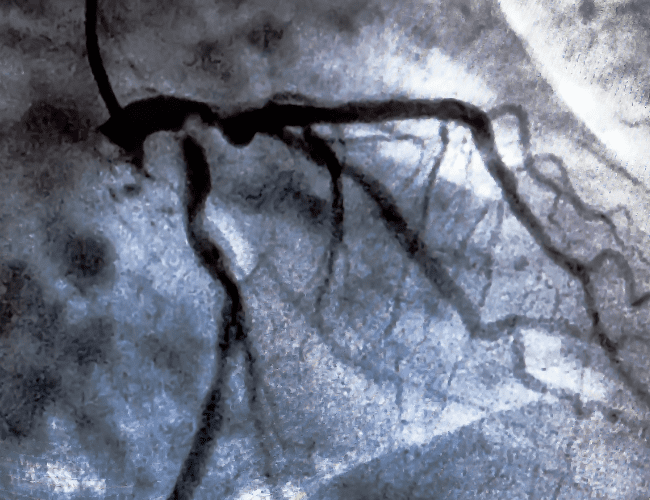

Cardiología intervencionista

Cardiología intervencionista en CDMX

El Dr. García Bonilla es un prestigioso cardiólogo intervencionista con amplios años de experiencia. Se especializa en enfermedades cardiovasculares, trastornos del ritmo cardíaco, enfermedades de la válvula cardíaca, e insuficiencia cardíaca.